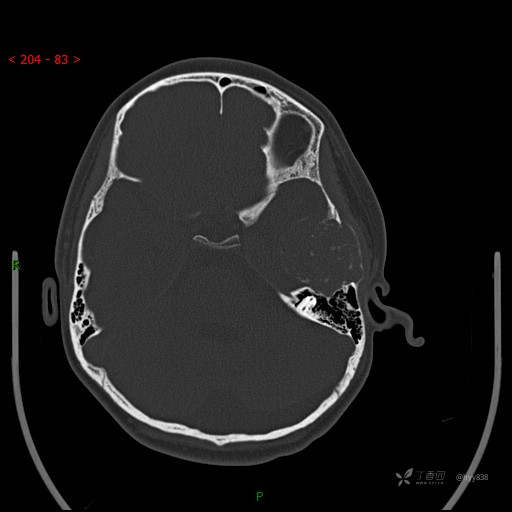

“典藏”病例分享。10岁儿童,头痛头晕一周余,CT、MRI 都有---结果公布~

简要病史:患者于一周前无明显诱因开始出现头痛头晕,无恶心呕吐,无肢体抽搐,无寒颤高热,无腹胀腹泻,无视力下降及视野缺损,上述症状休息后可稍缓解,未引起重视。 2天前患者头痛头晕不适加重,伴有恶心感,无呕吐,遂到当地人民医院行头颅CT检查示:左侧颞部占位性病变,今日家属为求进一步治疗,来我院门诊求治。门诊拟“左侧颞部占位性病变”收入我科。 患病以来,患者精神、饮食、睡眠尚欠佳,大小便如常,体力体重无明显变化。

临床诊断:左侧颞部占位

颅脑CT扫描